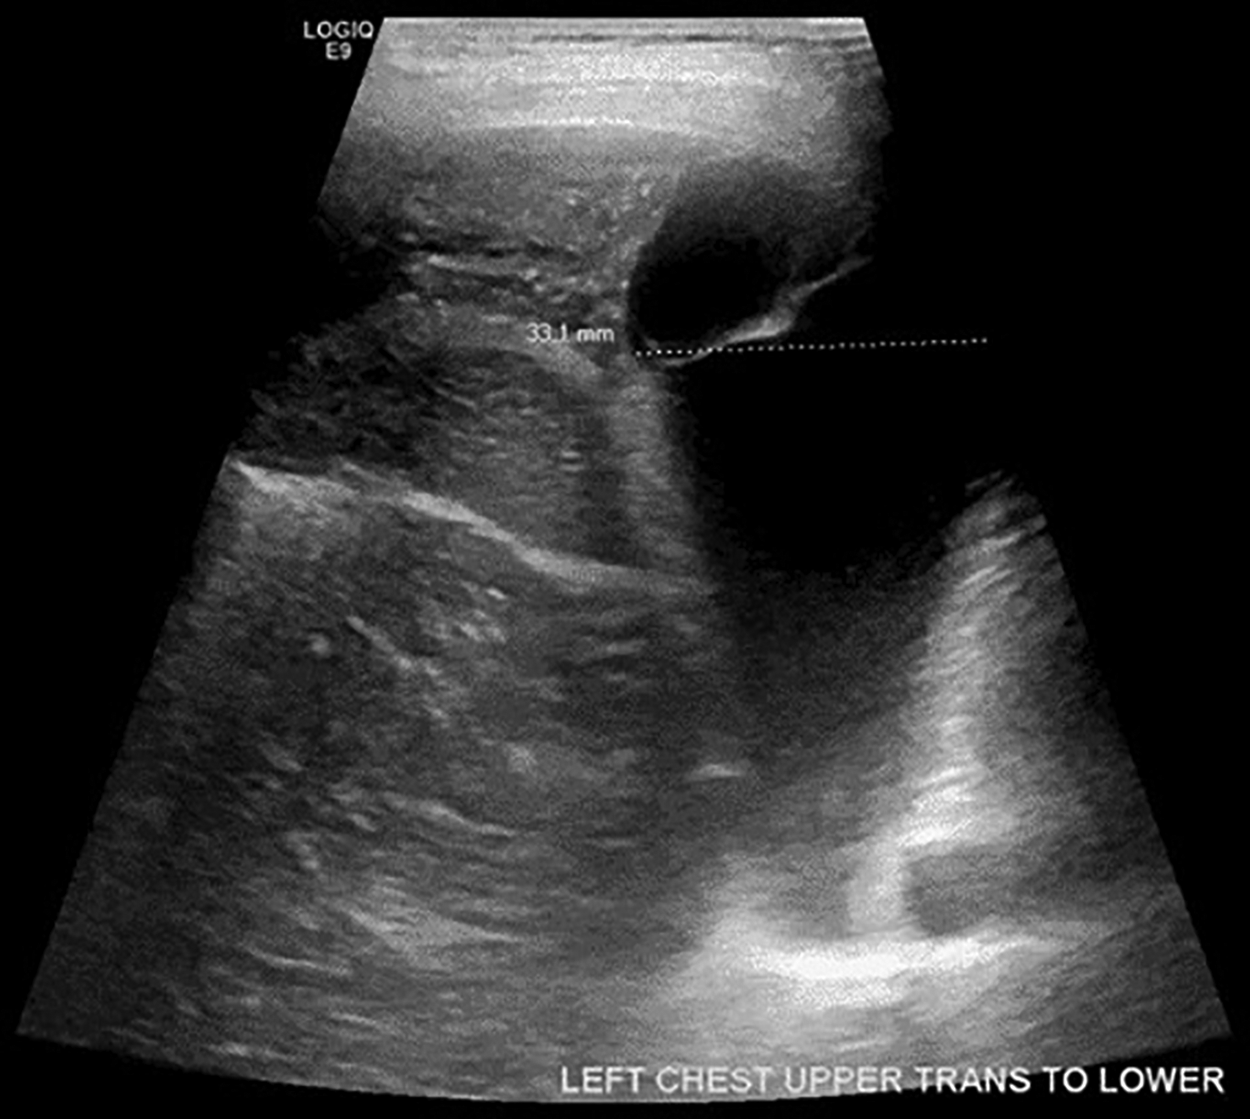

His post-TCPC course was complicated by a large chylous left pleural effusion confirmed by ultrasound (Figure 2) on POD 6. Echocardiogram (ECHO) demonstrated mild RV systolic dysfunction, mildly dilated right atrium and RV, mild TR, and mild neo-aortic insufficiency and no fenestration. Pulmonary edema and increased Fontan pressures (17–21 mm Hg) persisted despite diuretics and milrinone infusion. He subsequently developed methicillin resistant staphylococcus aureus (MRSA) sepsis and tricuspid valve endocarditis requiring intubation and escalation of vasoactive infusions, and ultimately peripheral cannulation for veno-arterial extracorporeal membrane oxygenation (VA ECMO) POD 10–11. At the time of cannulation Fontan pressures were 23–25 mmHg and he had a moderate-severely dilated RV with moderate-severely decreased RV systolic function, and moderate TR by ECHO. He was successfully decannulated after 7 days of ECMO. Fontan pressures were 21–28 mmHg following decannulation, a vegetation remained visible with persistent moderate TR. Further ECHO data is referenced in Table 1.

FIGURE 2

www.frontiersin.org

Figure 2.